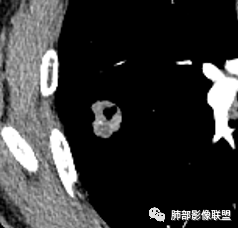

有空泡征,实性部分密度均匀?强化均匀?

内部血管怎么样?

看着内部强化比较散呢,结核一般不是周围强化,肉芽肿组织,内部如果是坏死物也会强化吗

晨读:男,67岁,体检发现右肺结节。近圆形,支气管及伴行血管进入结节,进入结节后支气管堵塞,血管走形尚自然,结节内血管边缘凹凸不平。远端边缘见毛刺(软毛刺?)及分叶。见胸膜牵拉。实变中见空洞。整体膨胀感不明显。考虑炎性肉芽肿可能,隐球菌病可能性大。注意鉴别鳞癌、结核。

虽然良恶性征象都有,但是这个病灶增强后坏死比较明显,如果是恶性:腺癌这样大小的结节坏死很少见,只有低分化腺癌可以坏死,但是低分化腺癌这种大小一般会有周围转移表现(叶间胸膜结节,癌淋或者淋巴结明显肿大),如果是鳞癌,收缩力,坏死情况以及没有支气管截断都不太支持,而且结节远端有几个小结节样改变,大家可能认为是血管,但我觉得应该是卫星灶。所以觉得隐球可能较大。壁胸膜的牵拉线也没有引起胸膜凹陷,比较纤细,至于病理中的丝状物不一定是真菌菌丝。

这个大部分边缘稍微偏平直一点,血管走行非常自然,包括里面的空泡征样的,影子很干净,边界很光滑,都是些炎性特点。

1.右肺上叶后段类圆形结节影,密度不均,有坏死空洞,坏死比较彻底,内外壁都较清楚。

4.病灶轻到中度强化。病灶内血管走行较完好,病灶旁血管局部显示粗大。

病灶内“旁若无人”的血管走形也让人难以理解。而该疑问也存在于结核病灶的辨析当中。